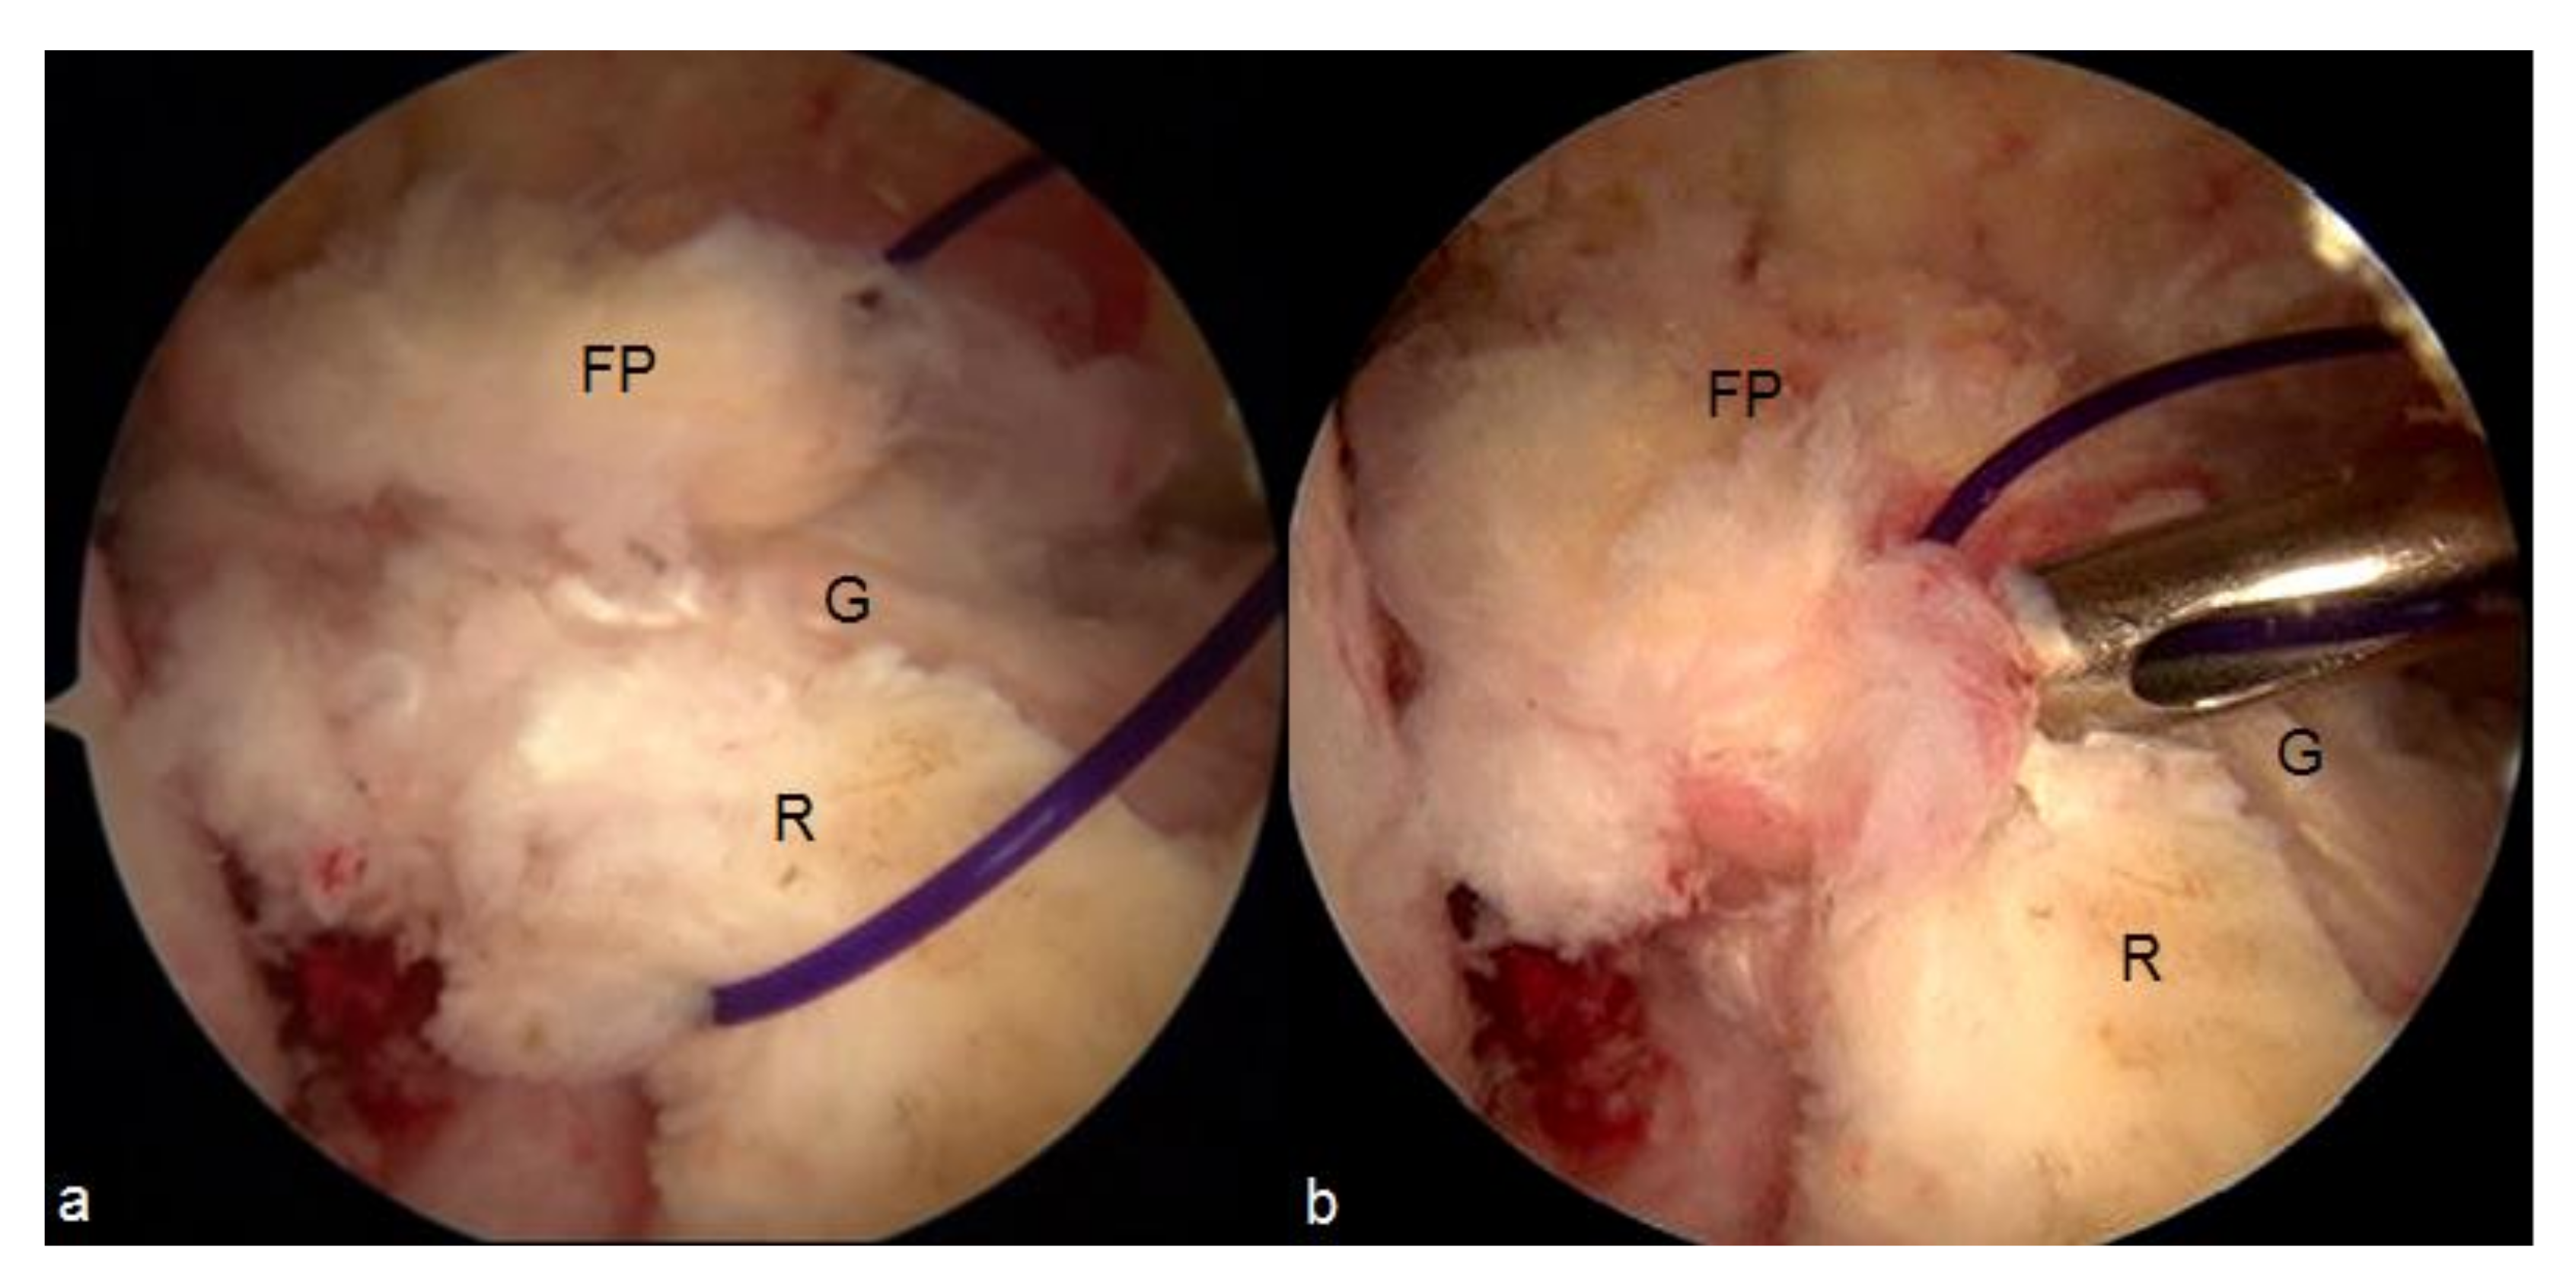

- Malinowski, K.; Ebisz, M.; Góralczyk, A.; Laprade, R.F.; Hermanowicz, K. Synovialization and Revascularization Enhancement in Repaired and Reconstructed ACL: PCL Fat Pad Transfer Technique. Arthrosc. Tech. 2020, 9, e1559–e1563. [Google Scholar] [CrossRef] [PubMed]